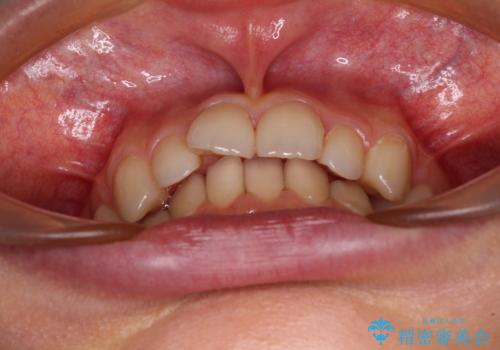

欠損や残存乳歯、深い咬み合わせ ワイヤー矯正で咬合改善

- 後続永久歯の欠損によるスペースと残存乳歯、深い咬み合わせを気にして来院された患者様です。

乳歯を残し、欠損部位のスペースを適正な幅に拡大し、インプラント補綴治療により歯列を整える治療も考えられましたが、ご本人から飛び出している前歯をどうしても引っ込めたいとの要望があったため、残存乳歯ならびに上顎左右第二小臼歯を抜歯して、歯列を整えることとしました。

甚大な咬合力に抵抗して過蓋咬合を改善する必要があり、更には口元が引っ込みすぎることがないように仕上げていく必要もあったため、治療期間は3年を超えましたが、当初計画通りの仕上がりで治療を終えることができました。